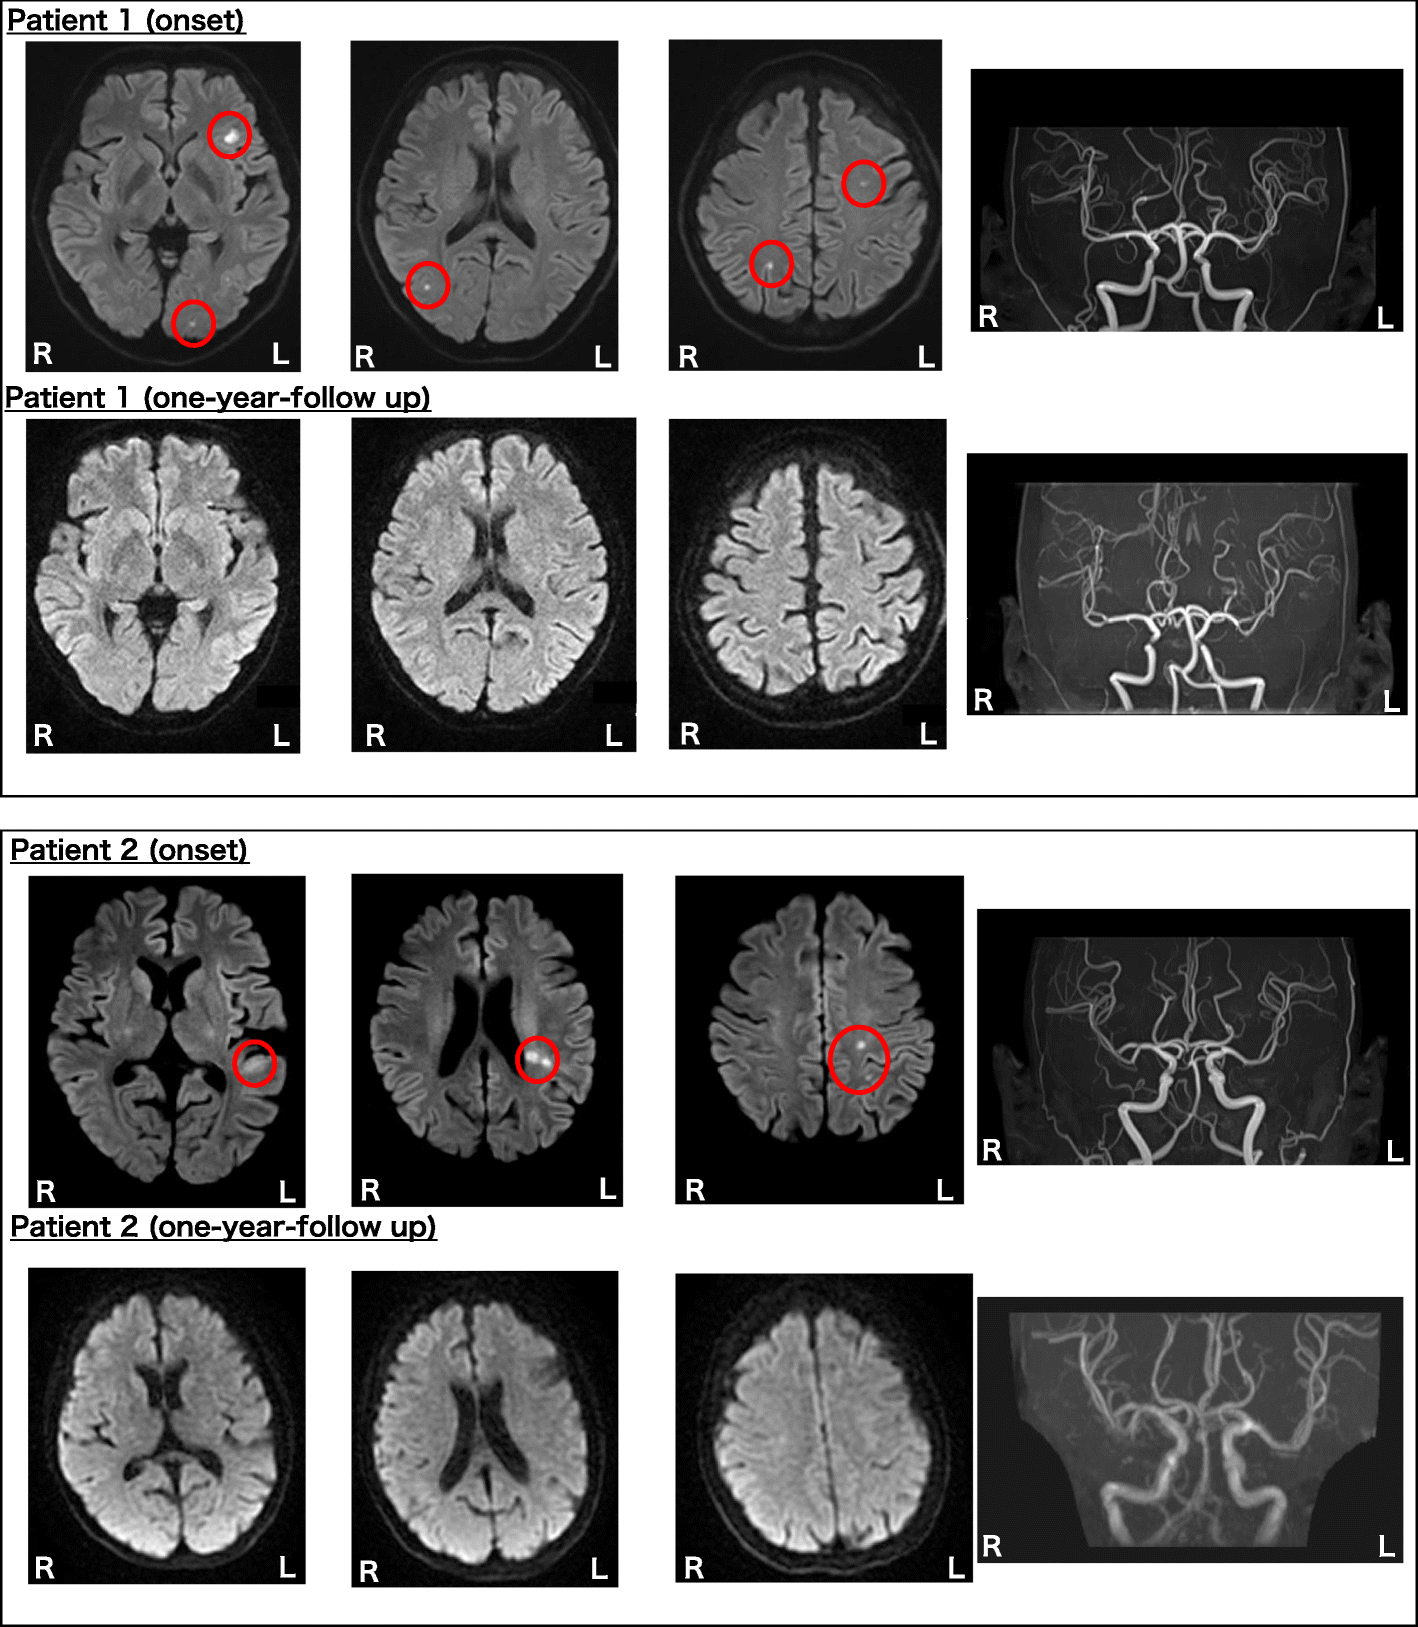

Fig. 1

Brain MRI (Patient 1, 2). Patient 1 (Upper row) Brain diffusion-weighted MRI revealed disseminated cortical infarctions bilaterally. MR angiography showed no arterial stenosis. (Lower low) Brain diffusion-weighted MRI and MR angiography (one year after the discharge) revealed no findings. Patient 2 (Upper row) Brain diffusion-weighted MRI revealed focal brain infarction in the white matter underlying the left temporal transverse temporal gyrus, the left supramarginal gyrus, and the left parietal cortex. MR angiography showed no arterial stenosis. (Lower low) Brain diffusion-weighted MRI and MR angiography (one year after the discharge) revealed no findings